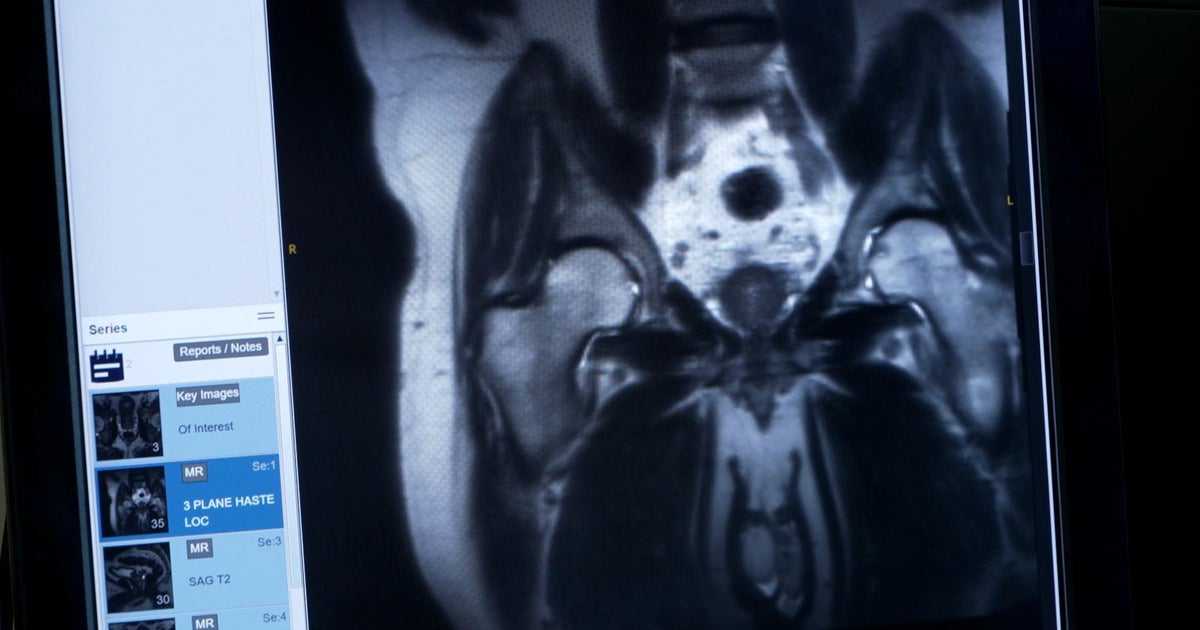

미드타운 신라이 의학교는 인공지능 사용을 채택하기로 결정했으며, 이로써 오픈AI의 교육 프로그램을 의료 및 대학원 학생들에게 제공하는 최초의 의료 스쿨이 되었다. 이 교육 프로그램은 의학 및 생명과학 분야의 학생들이 인공지능을 활용하여 학습하고 연구하는 것을 돕는다. 학생들은 이를 통해 의학 연구와 진단에 있어 혁신적인 방법을 습득하게 된다. 미드타운 신라이 의학교는 AI 기술을 적극적으로 활용하여 학생들이 미래 의료 현장에서 경쟁력을 갖출 수 있도록 지원하고 있다.